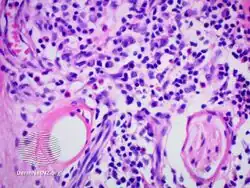

IgG4-related skin disease pathology